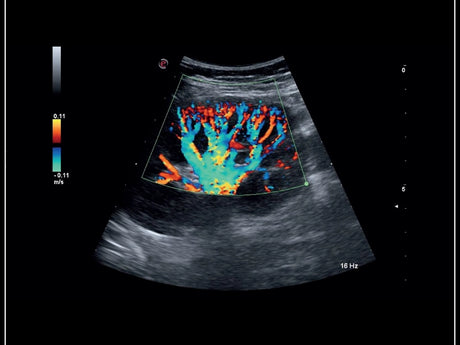

La qualité d’image est au cœur de la philosophie Esaote. Grâce à ses sondes de dernière génération et à son traitement du signal avancé, la marque permet une visualisation fine des structures anatomiques, même les plus profondes. Leurs échographes intègrent des écrans tactiles haute résolution, une interface claire et une connectivité complète, favorisant un flux de travail rapide et efficace.

Les échographes Esaote offrent une restitution d’image d’une grande précision, permettant un diagnostic fiable dans toutes les spécialités. Le traitement numérique optimise le contraste et la netteté, réduisant les artefacts et améliorant la détection des tissus pathologiques. Ces performances sont particulièrement appréciées en gynécologie, où la lisibilité des structures pelviennes ou obstétricales est déterminante.